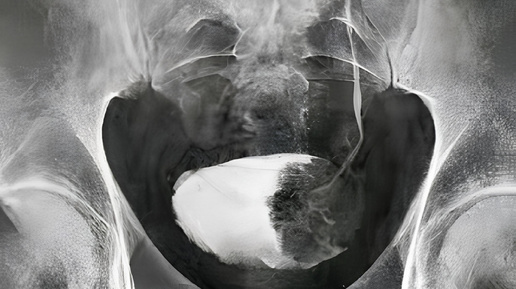

Материал носит исключительно информационно-ознакомительный характер. Он не может заменить очную консультацию специалиста, диагностику или лечение. При любых симптомах, вопросах или сомнениях необходимо обратиться к врачу. Самолечение может быть опасно для вашего здоровья. Материал подготовила врач-нефролог, трансфузиологом Александра Куликовская. Микционная цистография — это важный рентгенологический метод исследования, который используется для диагностики заболеваний мочевого пузыря и мочевыводящих путей...